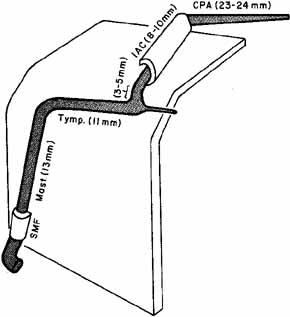

the facial vestibulocochlear nerve complex. Neurosurgery 6:483, 1980. 11. Guerrier Y: Surgical anatomy, particularly vascular supply of the facial nerve. In Fisch U (ed): Facial Nerve Surgery. Birmingham: Aesculapius Publishing Co., 1977: 12–23 12. Davis RA, Anson BJ, Puddinger JM, Kurth RE: Surgical anatomy of the facial nerve and parotid gland based upon a study